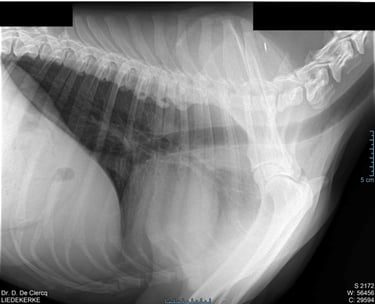

Hartonderzoek - Echocardiografie - Electrocardiografie (EKG) - Radiografie

Radiografie (RX)

Een RX is geschikt om botbreuken, een longontsteking, de hartgrootte, arthrose,....op te sporen.

Als de hond - kat niet lang genoeg stil kan blijven liggen dan is een verdoving noodzakelijk. Voor RX van het heupgewricht is een volledige verdoving noodzakelijk.